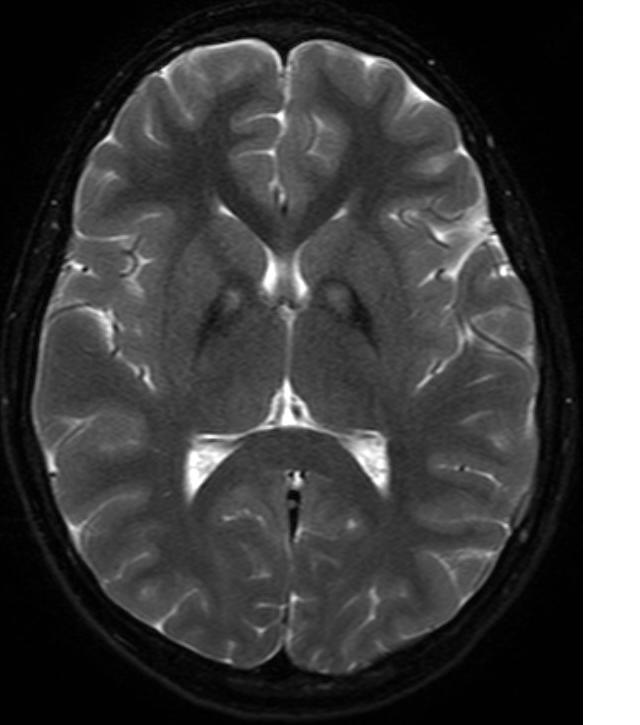

Neurodegeneracja związana z kinazą pantotenianu to rzadkie schorzenie neurologiczne, które jest wynikiem mutacji w genie PANK2, odpowiedzialnym za produkcję enzymu kinazy pantotenianu. Enzym ten odgrywa kluczową rolę w metabolizmie koenzymu A, który jest niezbędny dla wielu procesów biochemicznych w organizmie, w tym dla syntezy lipidów oraz metabolizmu energetycznego. Zaburzenia w funkcjonowaniu tego enzymu prowadzą do akumulacji toksycznych metabolitów, co z kolei przyczynia się do degeneracji neuronów.

Choroba ta charakteryzuje się różnorodnymi objawami, które mogą obejmować problemy z ruchem, zaburzenia poznawcze, a także zmiany w nastroju i zachowaniu. W miarę postępu choroby, pacjenci mogą doświadczać coraz większych trudności w codziennym funkcjonowaniu, co znacząco wpływa na jakość ich życia. Neurodegeneracja związana z kinazą pantotenianu ma tendencję do występowania w młodym wieku, a jej przebieg może być zróżnicowany, co sprawia, że diagnoza i leczenie są skomplikowane.